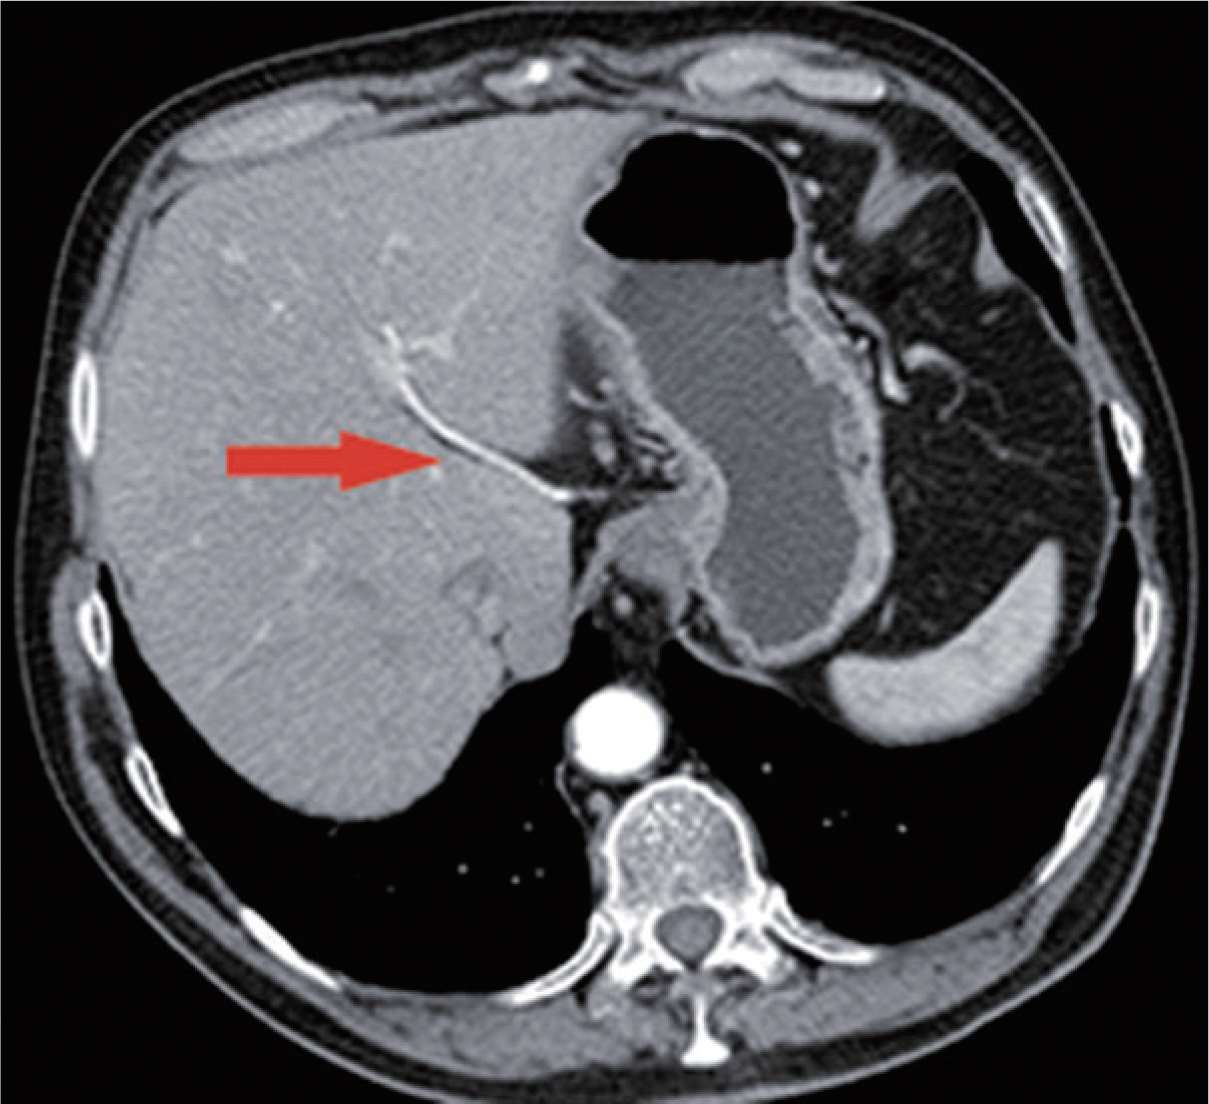

图2-36 结扎胃左动脉、静脉时,需小心可能存在的发自胃左动脉的副肝左动脉,这种变异的肝左动脉出现率为11.5%。术前CT扫描动脉成像可清楚显示变异的肝左动脉(红色箭头)。